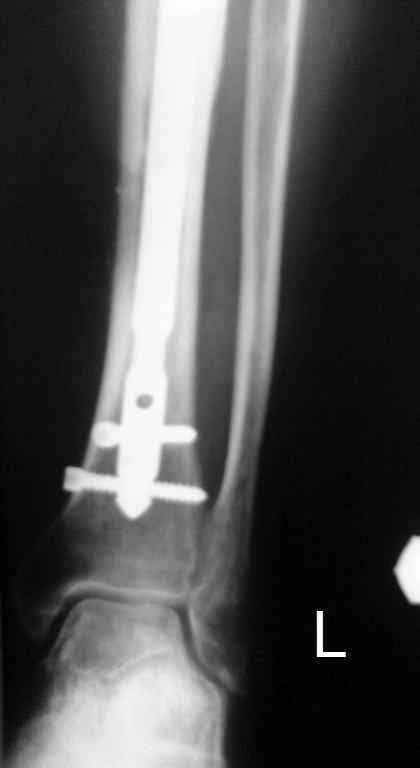

Выкладываю картинки похожей пациентки. Извините, что без окончательных снимков (сейчас их нет под рукой). Правда мы имели проблемы у данной больной после снятия аппарата, когда промежуточный фрагмент большеберцовой кости сместился на 1,5 см дистально и отошел от проксимальной части кости. До сих пор у пациентки на снимках определяется лишь тонкая полоска кости по задней поверхности за штифтом (образовалось что-то вроде маленького регенерата)в области стыковки промежуточного и проксимального фрагментов. Больная пока решила подождать. Не хочет оперироваться, так как ходит не хромая, работает.